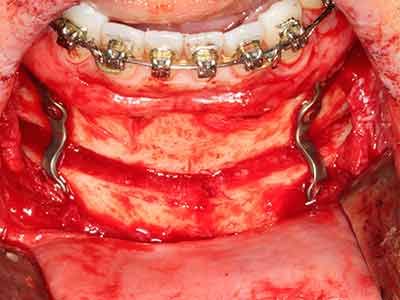

Fig. 13: Adequate irrigation with the 4-mm residual bone width is essential for this 52-year-old patient during the bone splitting.

Fig. 14: Placement of four tapered RSX implants (Bego Implant Systems, Bremen).